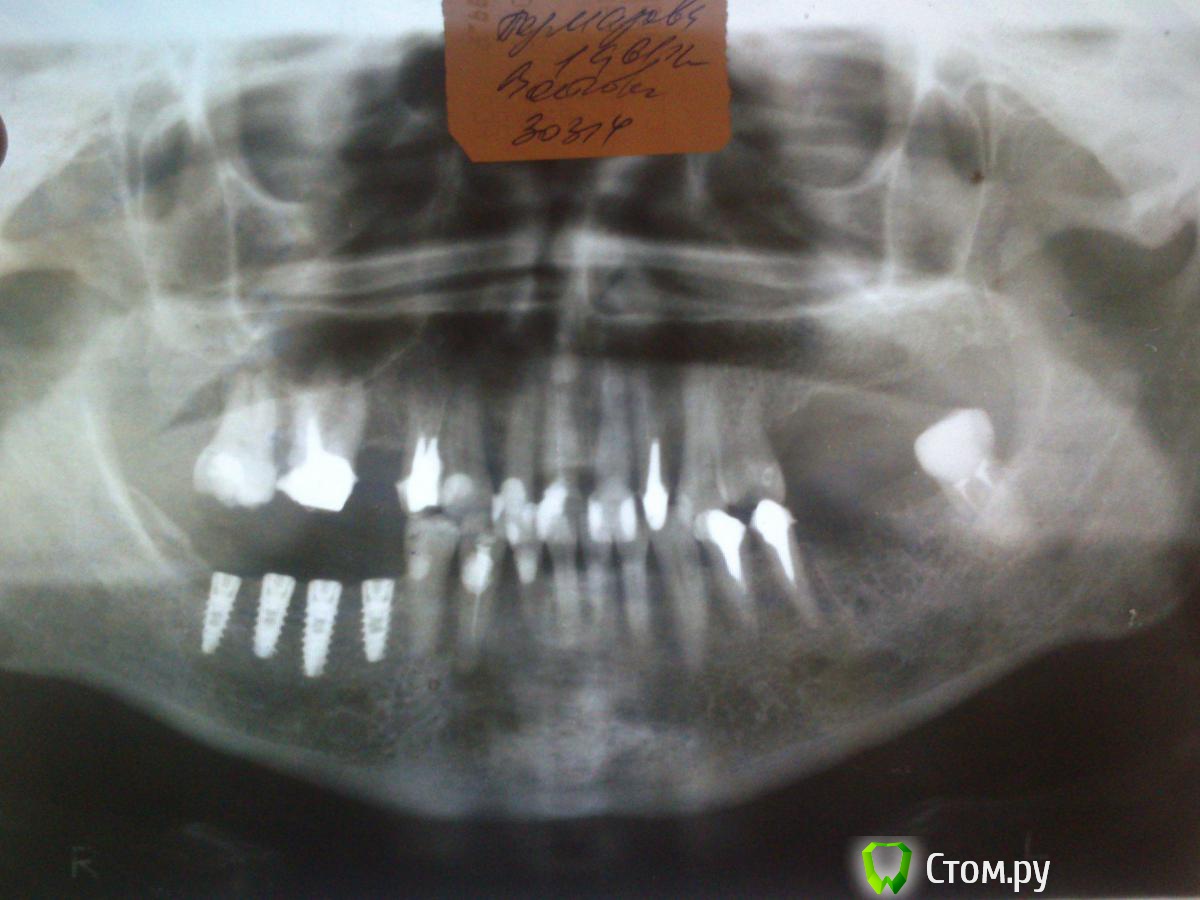

GoDemon Опубликовано 30 сентября, 2014 Поделиться Опубликовано 30 сентября, 2014 Здравствуйте, коллеги. Ситуация такая, пациентке ставил импланты пол года назад, альвеолярный отросток визуально узкий, не был уверен, что вообще получится хоть что-то туда установить. Когда раскрылся, оказалось, что места не разгуляешься , но хватает . Поставил тогда четыре импланта , мис - севен: 3,75-10, 4,2-11,5, 4,2-10, 3,75-10 . На следующий день все ок, а дальше сложности. Когда пришла снимать швы, в области двух центральных винтов видны заглушки. Я деэпителизировал края, ушился заново, основательно, в два слоя, и все равно, когда надо было швы снимать, заглушка одного импланта была видна... Оставил так, и она затянулась ( я уже значительно позже прочитал на форуме , что нужно было фдм-ки ставить... Ну да ладно... Пациентку вообще протезировать не я должен был, подготовка к протезированию не мной проводилась, вкладки тоже не мои... Но вскоре ее отправили, сказали, что слева тоже зубы не надежные, мосты ставить на них нельзя, пусть доктор ставит импланты и протезирует, раз уже начал... Слева гребень был шире, но когда раскрылся , оказалось, что вестибулярно в позиции 3.6 отсутствует кортикалка, а в самой лунке что-то типа фиброзной ткани... Я попытался кость восстановить, и, к моему удивлению, получилось. Через четыре месяца после аугментации поставил там два импланта, но на снимке увидел атрофию в области имплантов справа... Огорчение на целый день, блин... Сам думаю, что близко друг к другу поставил, может заглушка прорезовшаяся повлияла, или, может, все же гребень узковат был( правда все импланы были костью окружены достаточно, как мне казалось) ... Подскажите пожалуйста, в чем, на ваш взгляд, главная причина и что теперь делать , можно ли на них протезировать, или надо убирать? Стоят они неподвижно, Имплантов самих не видать, фдм -ы в десну погружены... Спасибо всем, кто осилит столько букв, и даст совет) И , традиционно, прошу прощение за качество приложенных рентгенограмм) Ссылка на комментарий

TIGER Опубликовано 1 октября, 2014 Поделиться Опубликовано 1 октября, 2014 НА 2 снимке заметна резорбция кортикалки в 4 сегменте,торк большой был? Ссылка на комментарий